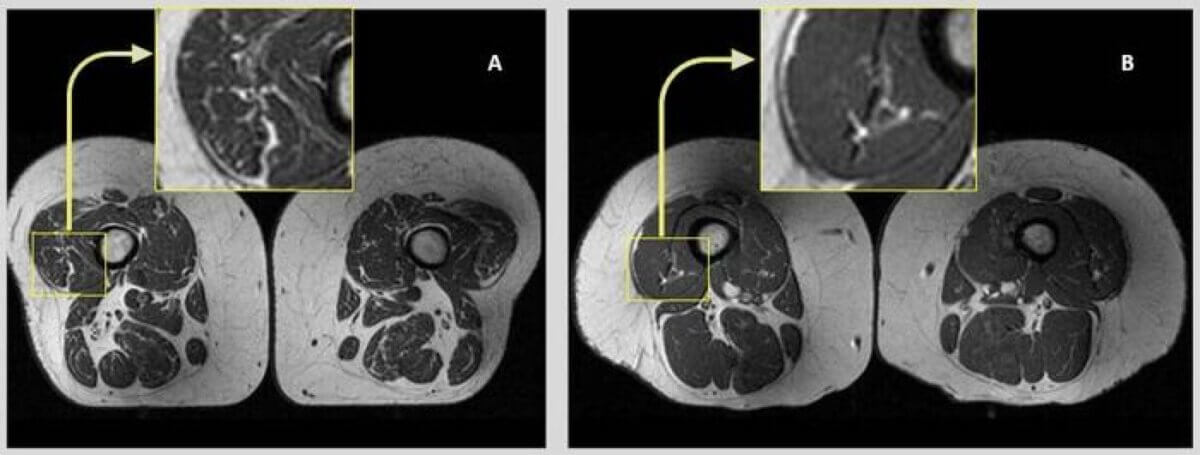

Using magnetic resonance imaging (MRI), researchers made a fascinating discovery. The more ultra-processed foods participants consumed, the more fat accumulated inside their thigh muscles. Critically, this relationship held true across different variables – it didn’t matter if participants were physically active or couch potatoes, consumed more or fewer calories, or had different body types.

“Research from our group and others has previously shown that quantitative and functional decline in thigh muscles is potentially associated with onset and progression of knee osteoarthritis,” Dr. Akkaya continues. “On MRI images, this decline can be seen as fatty degeneration of the muscle, where streaks of fat replace muscle fibers.”